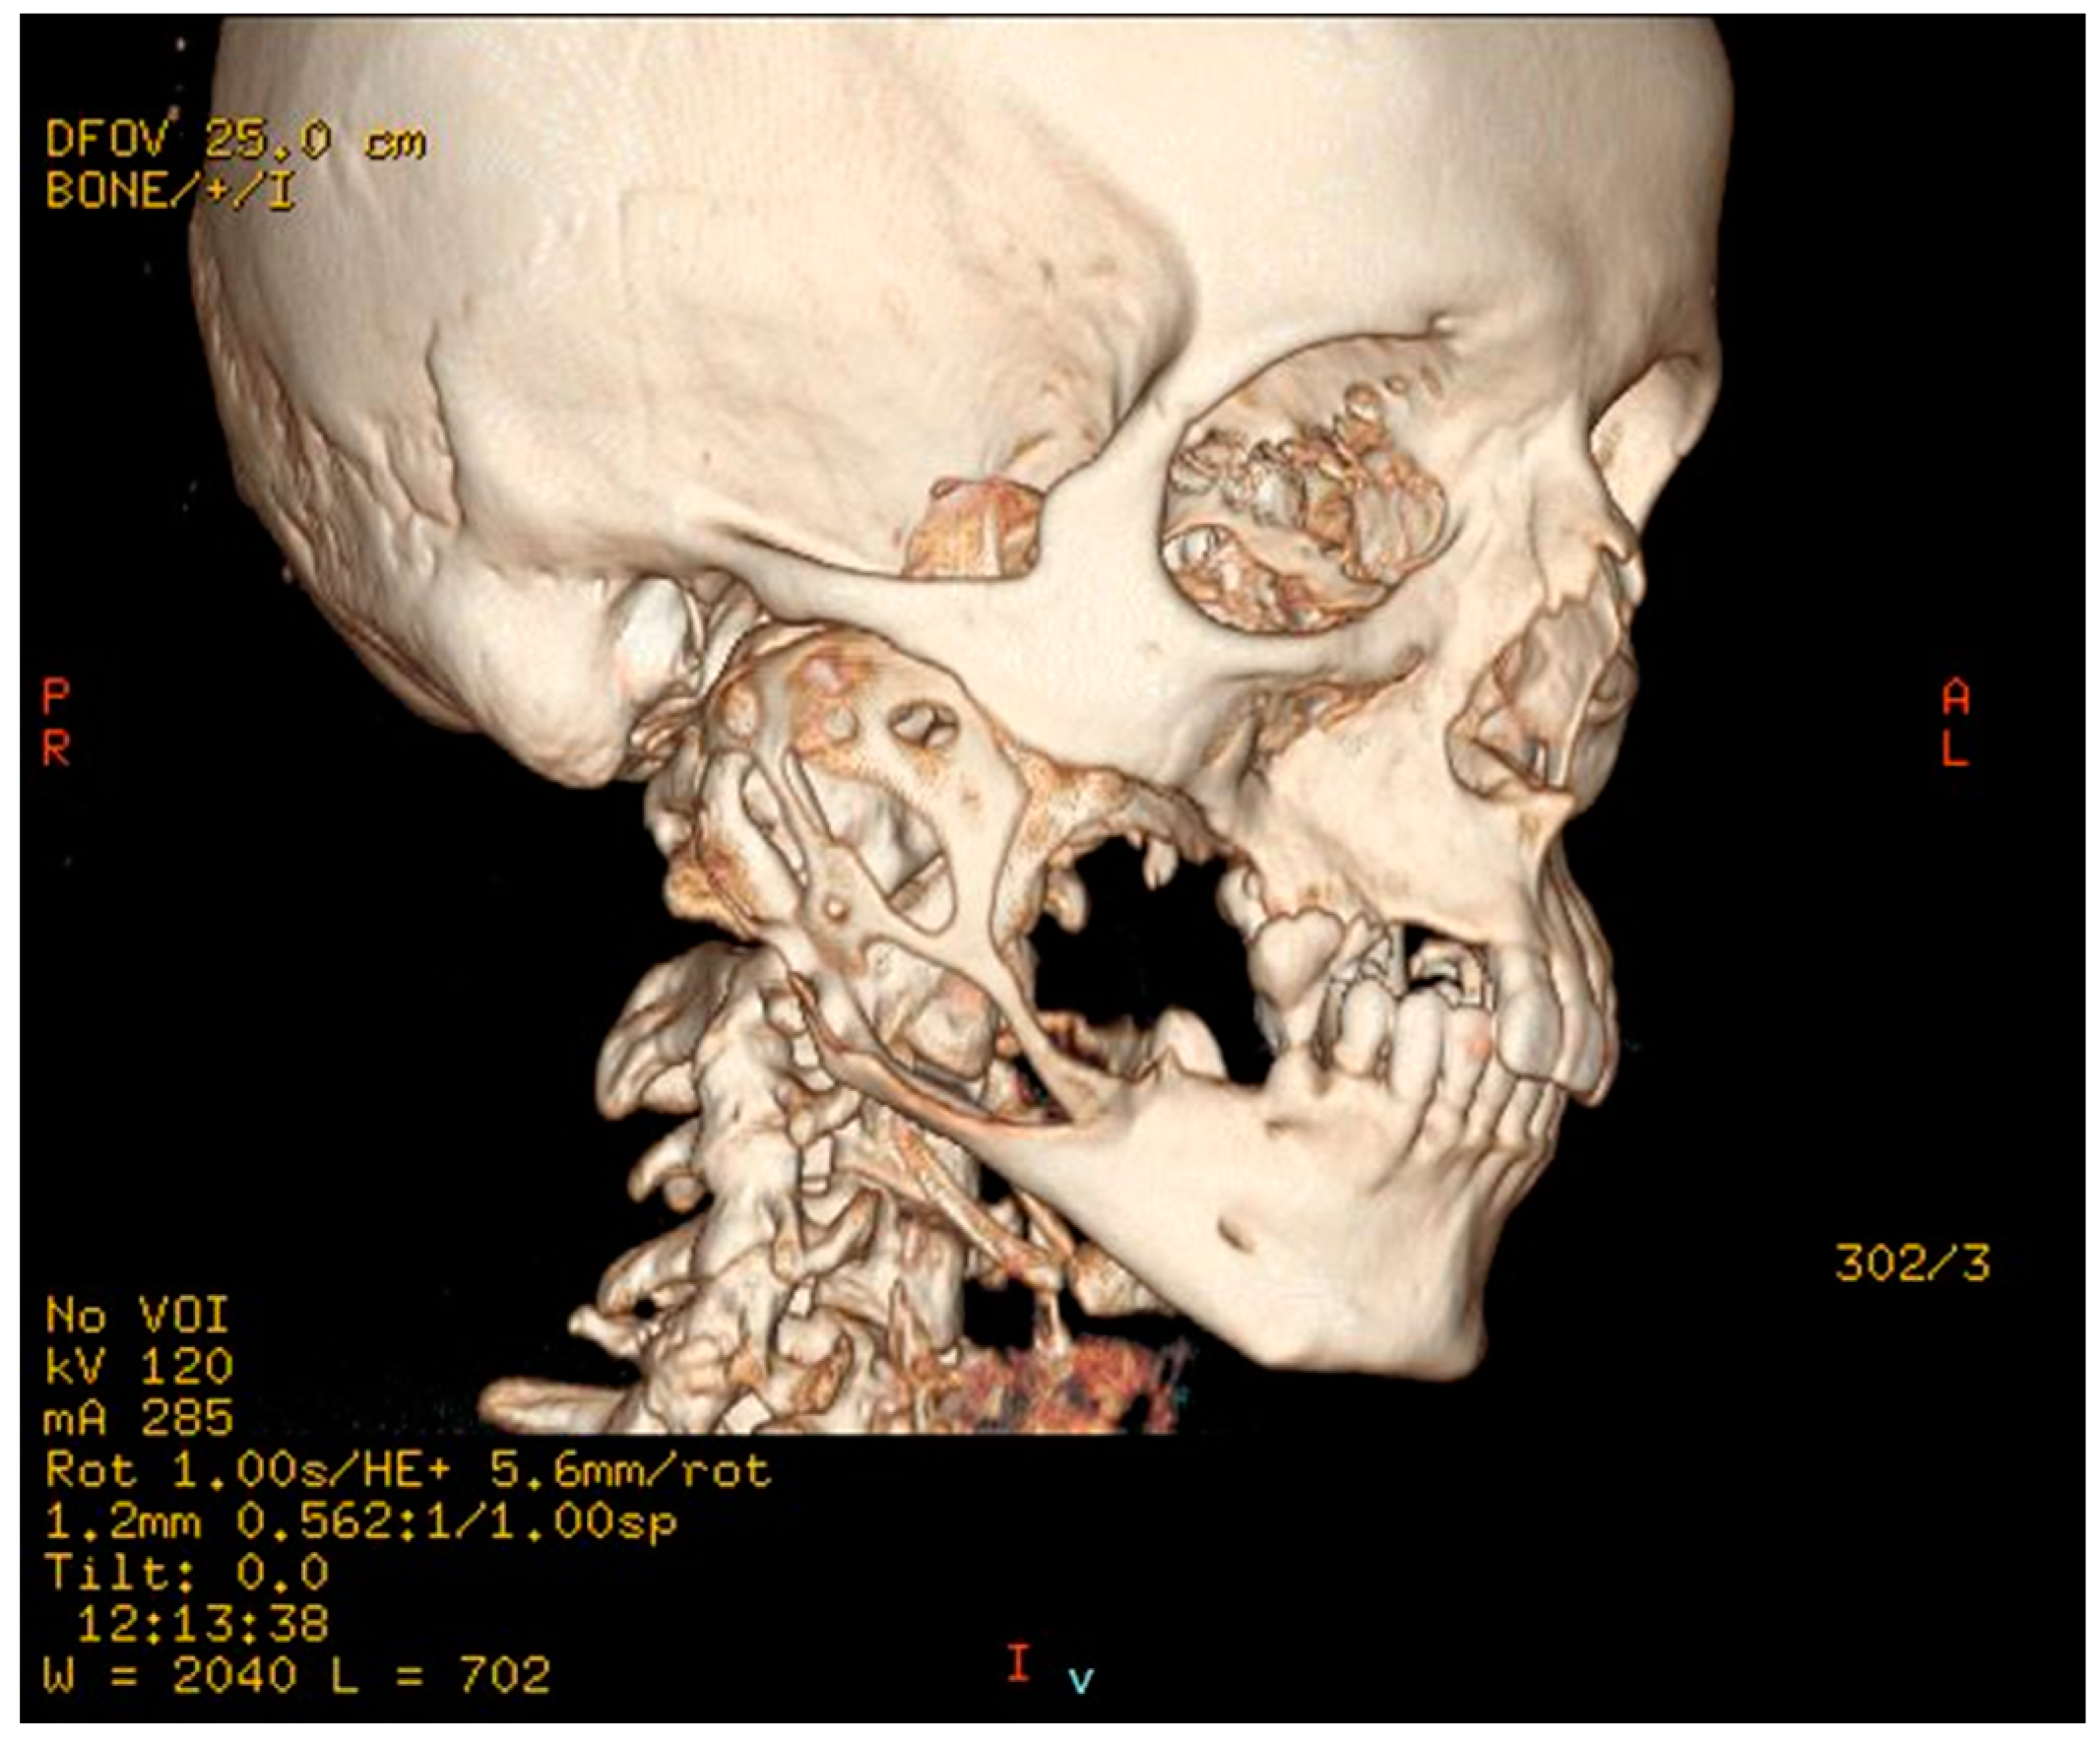

2.1. Patient #1